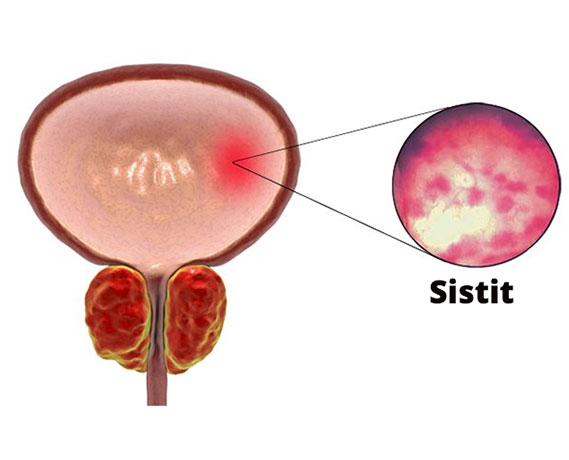

- Sık idrara çıkma

- İdrar torbasını boşaltmada güçlük hissi

Myomların klinik bulguları genellikle lokalizasyonları ile ilişkilidir. Rahim kavitesinin içine doğru büyüyen submüköz myomlar, uzamış ve ağır kanamaya neden olurlar. Bu myomlar aynı zamanda gebe kalmak isteyen kadınlarda da problem yaratırlar. Subseröz myomlar ise rahimin dış kısmına doğru büyüyen myomlardır. Bazen mesaneye bası yaparak idrar ile ilgili şikayetlere neden olabilirler. Eğer rahmin arka tarafına doğru büyürlerse rektuma bası ile kabızlık, spinal sinirlere bası ile bel ağrısına neden olabilirler.